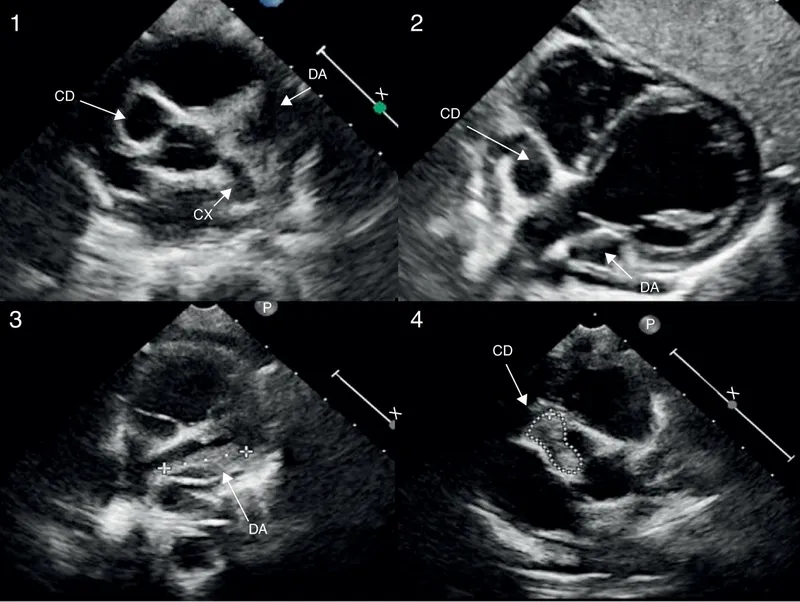

- The most critical long-term complication of Kawasaki Disease, affecting 15-25% of untreated children.

- Pathology involves necrotizing arteritis, destroying the tunica media and internal elastic lamina, leading to aneurysm formation.

- Primary Sequela: Coronary Artery Aneurysms (CAA).

- Can lead to thrombosis, stenosis, & myocardial infarction (MI).

- Coronary artery aneurysms (CAA) are the most feared long-term complication.